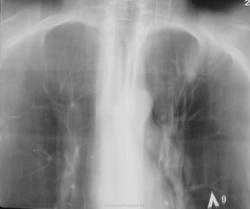

Вызванный в терапевтическое отделение фтизиатр (для консультации) назначил томографию.

Пациента довольно успешно лечили по поводу "пневмонии", да и субъективно пациент отмечал улучшение, НО перед выпиской, ВДРУГ, при микроскопии были обнаружены МБТ.

Решили "чиркнуть" боковые томограммы.

Договорена консультация и госпитализация в ОПТД. По просьбе коллеги фтизиатра делам томограммы в прямой проекции.

Д/д ряд: пневмония, саркоидоз и м.б. туберкулез.

3 посева на БК для исключения инфильтративного туберкулеза. для пневмонии температурка низковата, согласны? )

Туберкулезными палками пахнет...

Вызванный в Т.О. фтизиатр (для консультации) назначил линейную томографию.

Коллега фтизиатр находится в растрепанных чувствах, настаивает на томографии в прямой проекции.

Госпитализирован в ОПТД. Проводится специфическое лечение, но ВИЧ выявлен не был.

Динамика в процессе лечения.